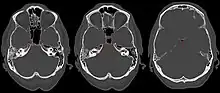

| Apicitis petrosa as seen in computed tomography | |

In persons with longstanding ear infection and typical symptoms, medical imaging such as CT or MRI of the head may show changes that confirm disease involvement of the petrous apex of temporal bone.